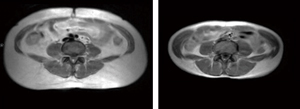

内視鏡と 最新のMRI機器による 計測でも 脂肪の消滅が 実証されました ![]() このように驚異的な 脂肪の減少を記録 さらに ▼ ▼ ▼ 毛細血管に入り込んだ ミクロの脂肪マデ 溶解を確認 血液の質が変化し ![]() サラサラ血液に!! ↓↓↓ 代謝UP!! 蓄積された 頑固な脂肪が 細胞レベルで減少 |

| 腸内環境を整えることで、代謝がUPし、脂肪が燃焼。さらに、配合されている有効成分が 脂肪を溶かす!! 脂肪細胞レベルでの 減少が発生!! ![]() ※赤い部分が脂肪細胞 ↓↓↓↓ CT測定でも 痩身の減少が ハッキリと確認!! ![]() ↓↓↓↓ どんな脂肪でも 【溶解】 |